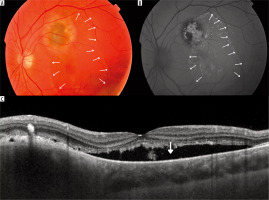

Figure 3

Giant nevi in 58-year-old patient, located close to the optic disc with drusen and no other risk factors for malignant transformation (T-F-S-O-M-DiM+): A) color fundus picture; B) fundus autofluorescence photography showing mildly hyperautofluorescent drusen (arrow); C) optical coherence tomography showing hyperreflective choroidal nevus (white arrows) with drusen (blue arrow) and its location close to the optic nerve